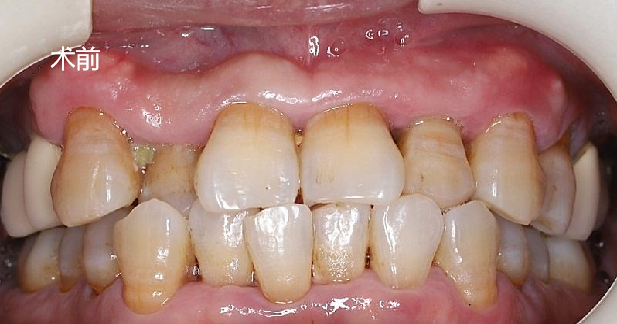

口内检查:全口牙龈轻度吸收,牙列不齐,12、22反合,口腔卫生一般。

主诉牙情况:22牙体颜色稍变暗,  松动 III 度,叩诊(-),牙 龈无红肿、溢脓、牙周袋 6mm,近远中龈乳头缺损。

术前术后对比